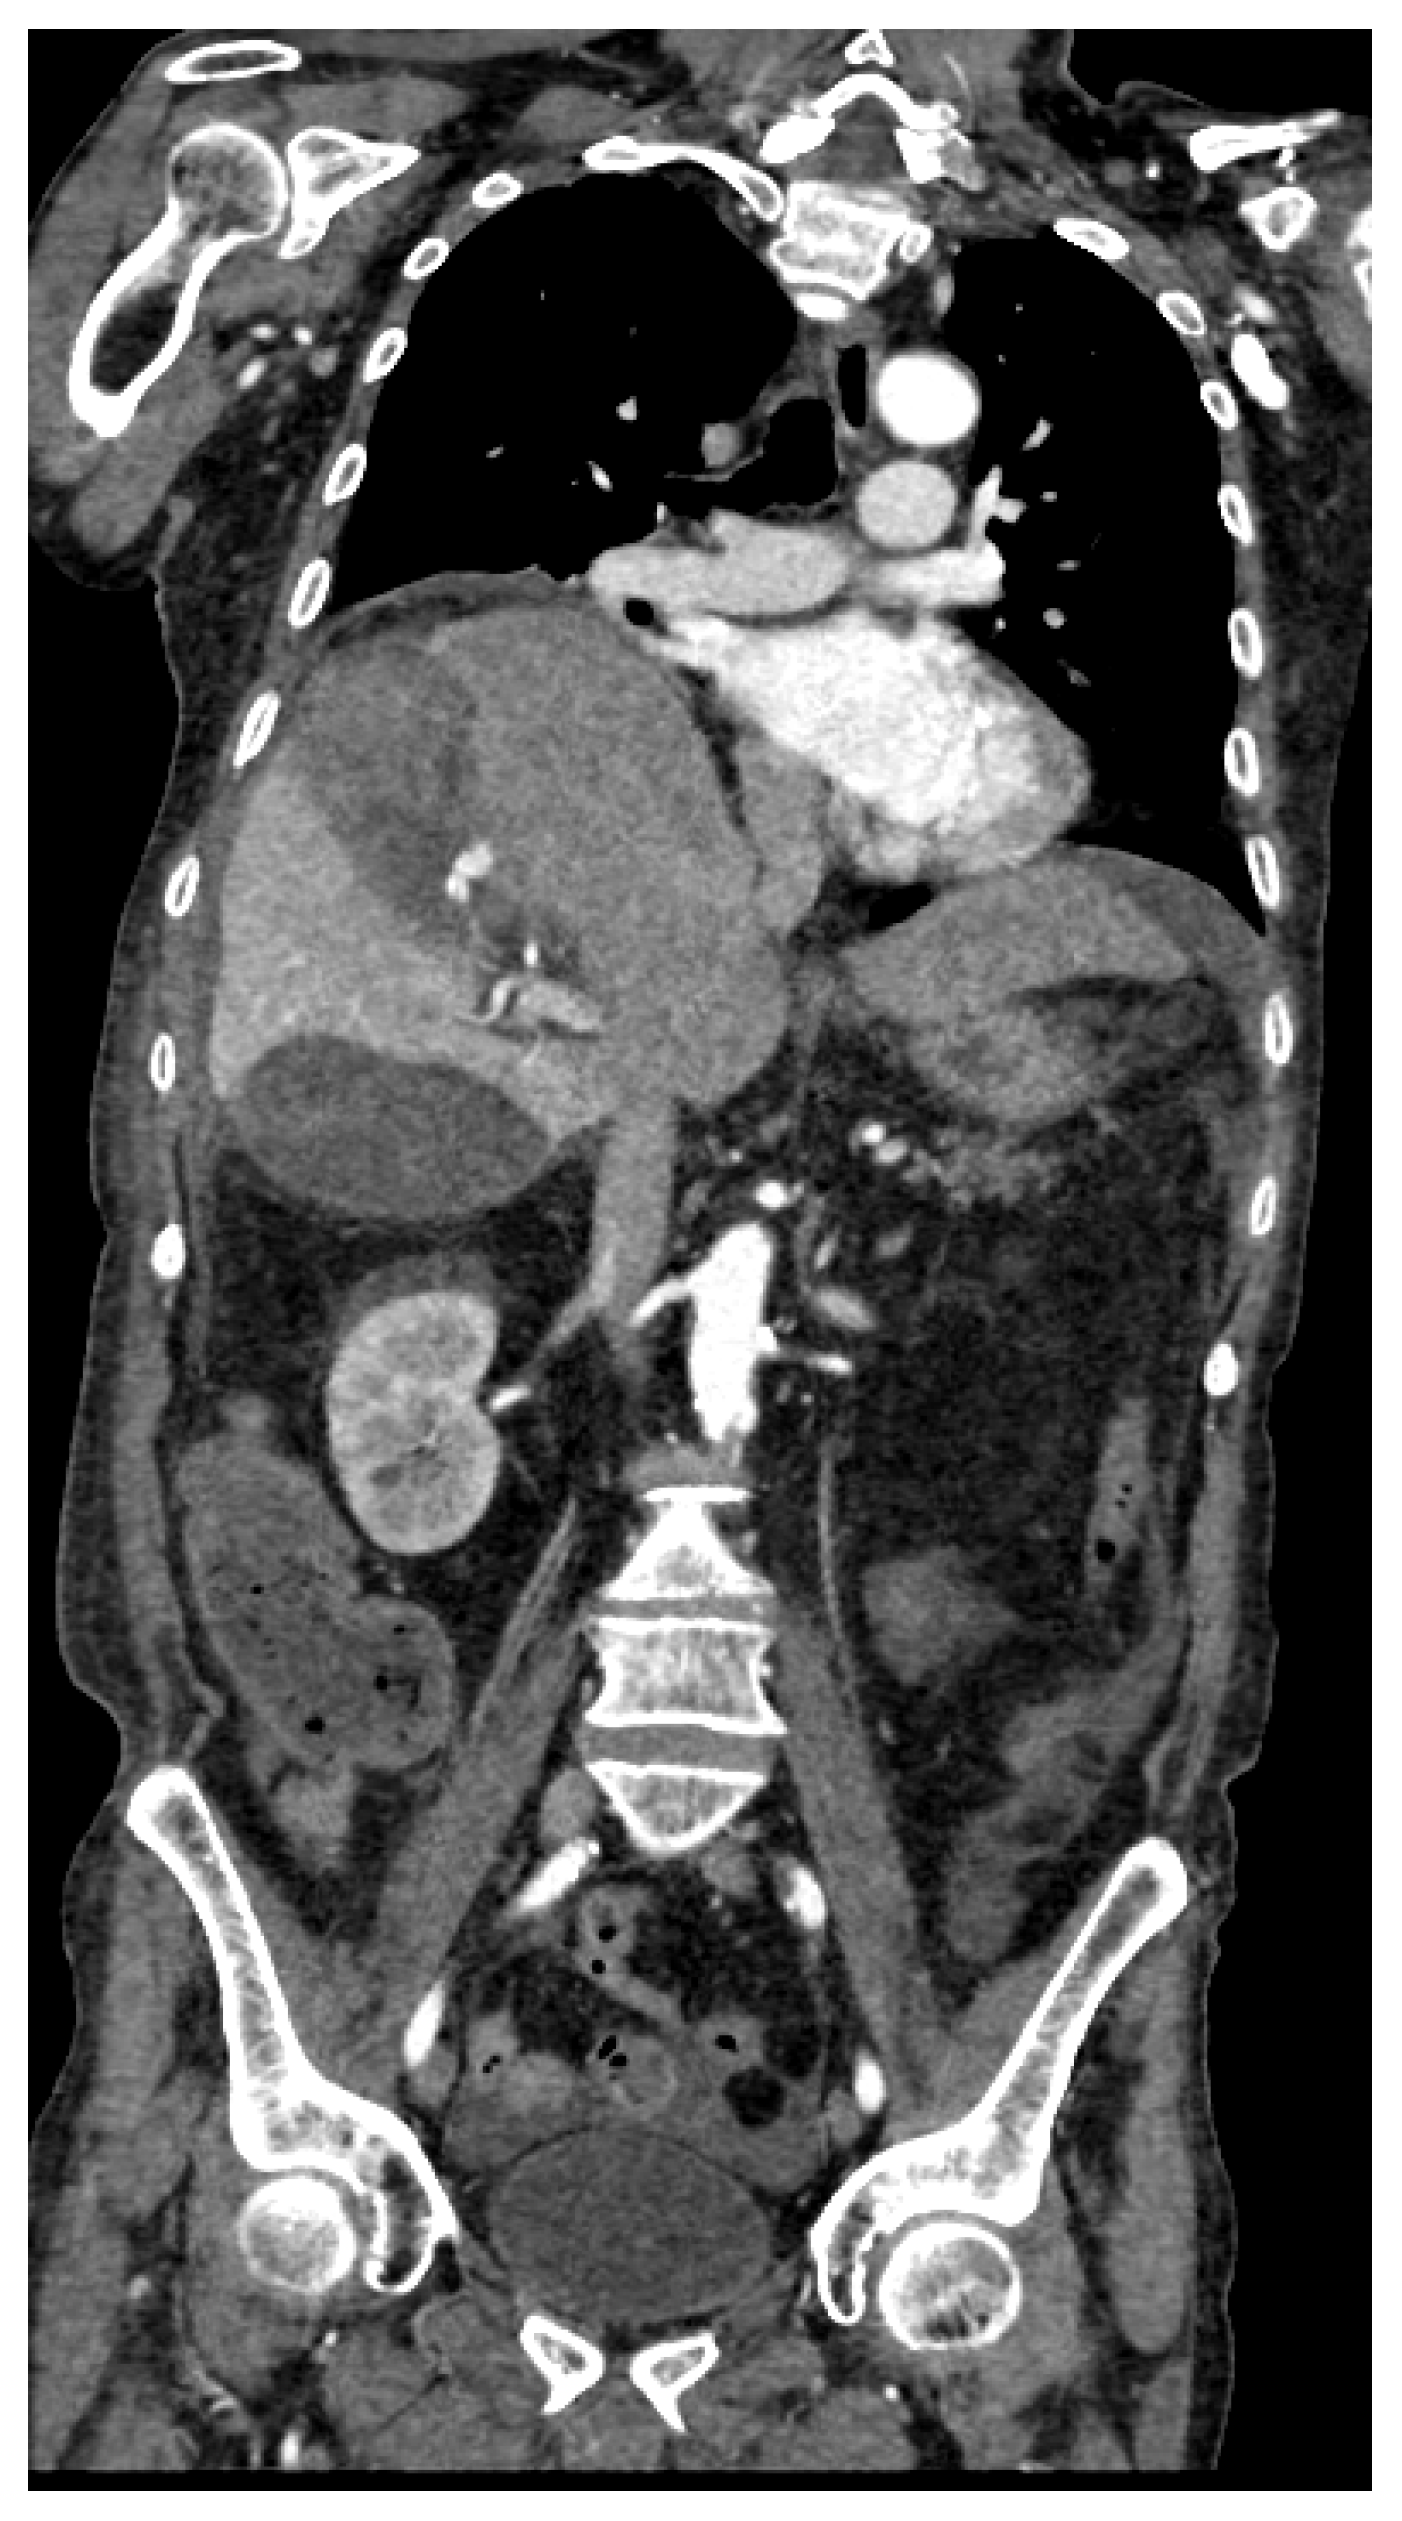

Figure 8.

MPR coronal (a) and sagittal (b) clearly demonstrate cystic branch pseudoaneurysm bleeding.